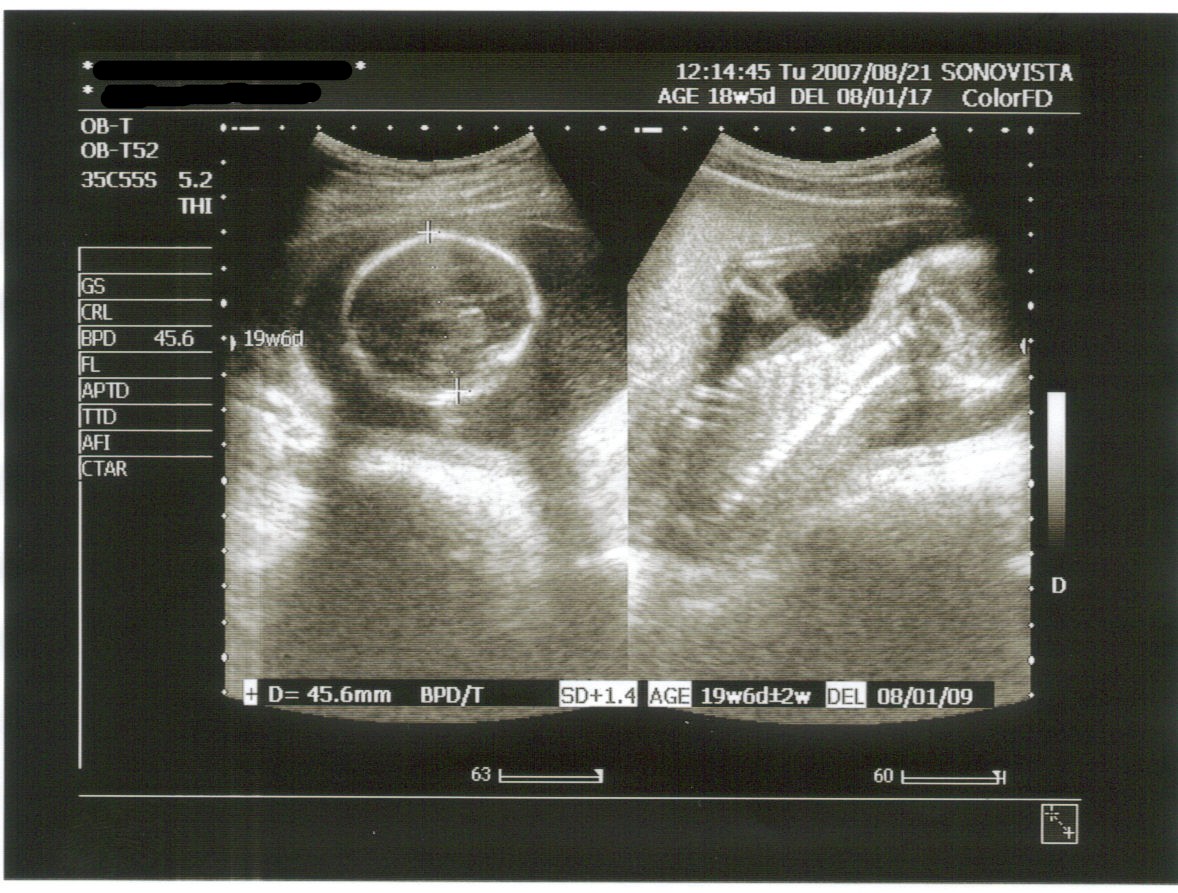

今日のお腹の中の様子は・・・

今日は逆子状態でした(-_-;)

左が頭で45.6㎜

右は背中側で背骨と肋骨が見えました。

指も5本ハッキリ見えましたよ。

推定体重は281g

狭い所にいるらしく脚のほうがなかなか見えなくて先生困ってました(^_^;)

体重って頭と胴の輪切りと太腿の骨の長さで算出されるんだってさ。

今日のエコーだと週相当20w4d。

現在の週数より少し大きめらしいけど、今はまだ細かく分からないんだって。

もう少し進むといろんなことが分かるらしい。

胎盤の位置も正常で、至って順調だってさ v(^-^)v